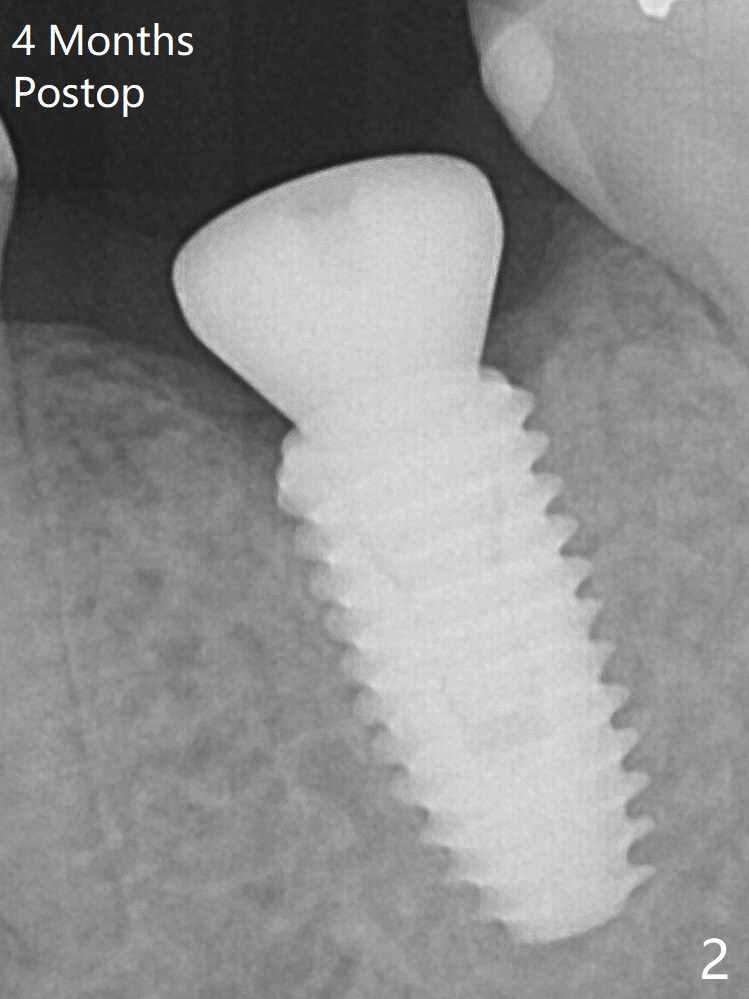

A 5x10 mm implant is intentionally placed distal at #19 using guided surgery (Fig.1).  When it is osteointegrated, it will be used as an anchorage to upright the tooth #18 orthodontically.  In fact the implant is mistakenly placed 1.5 mm deeper than planned without significant side effect (paresthesia).  The healing abutment dislodges (probably as related to deep placement of the implant) 20 days postop and is retightened.  There is mild crestal bone loss 4 months postop (Fig.2).